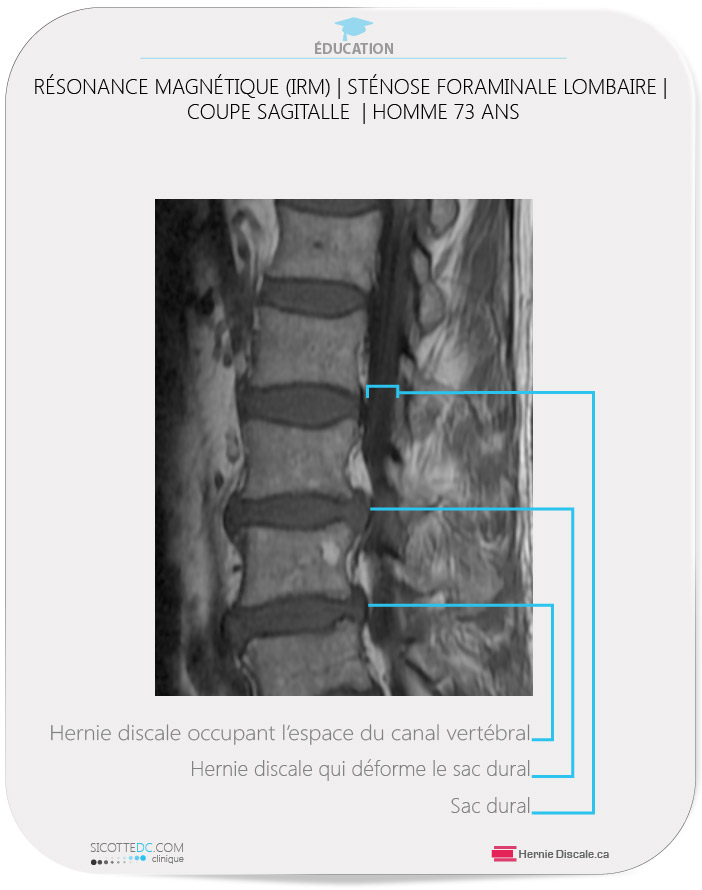

À l’arrivée à notre clinique, ce patient de 73 ans était sous l’effet de forte dose de morphine pour contrôler la douleur. Il ambulait avec difficulté. Le patient possédait une IRM au moment de la consultation. L’examen physique a révélé les faits suivants : sensation des membres inférieurs intacte, douleur en prédominance à la jambe droite et le fessier droit. Après dix jours de traitements avec la méthode Cox®, le patient pouvait dormir et marcher normalement.

RÉSONANCE MAGNÉTIQUE (IRM) | EXEMPLE DE STÉNOSE FORAMINALE LOMBAIRE | COUPE AXIALE

INTERPRÉTATION

- Ligament jaune : Le ligament jaune est hypertrophié. Ceci diminue la distance antéropostérieure du canal vertébral.

- Sténose foraminale sévère : La hernie discale importante déborde vers le foramen causant un pincement du nerf rachidien.

- Espace normal : Du côté opposé, l’espace est normal.